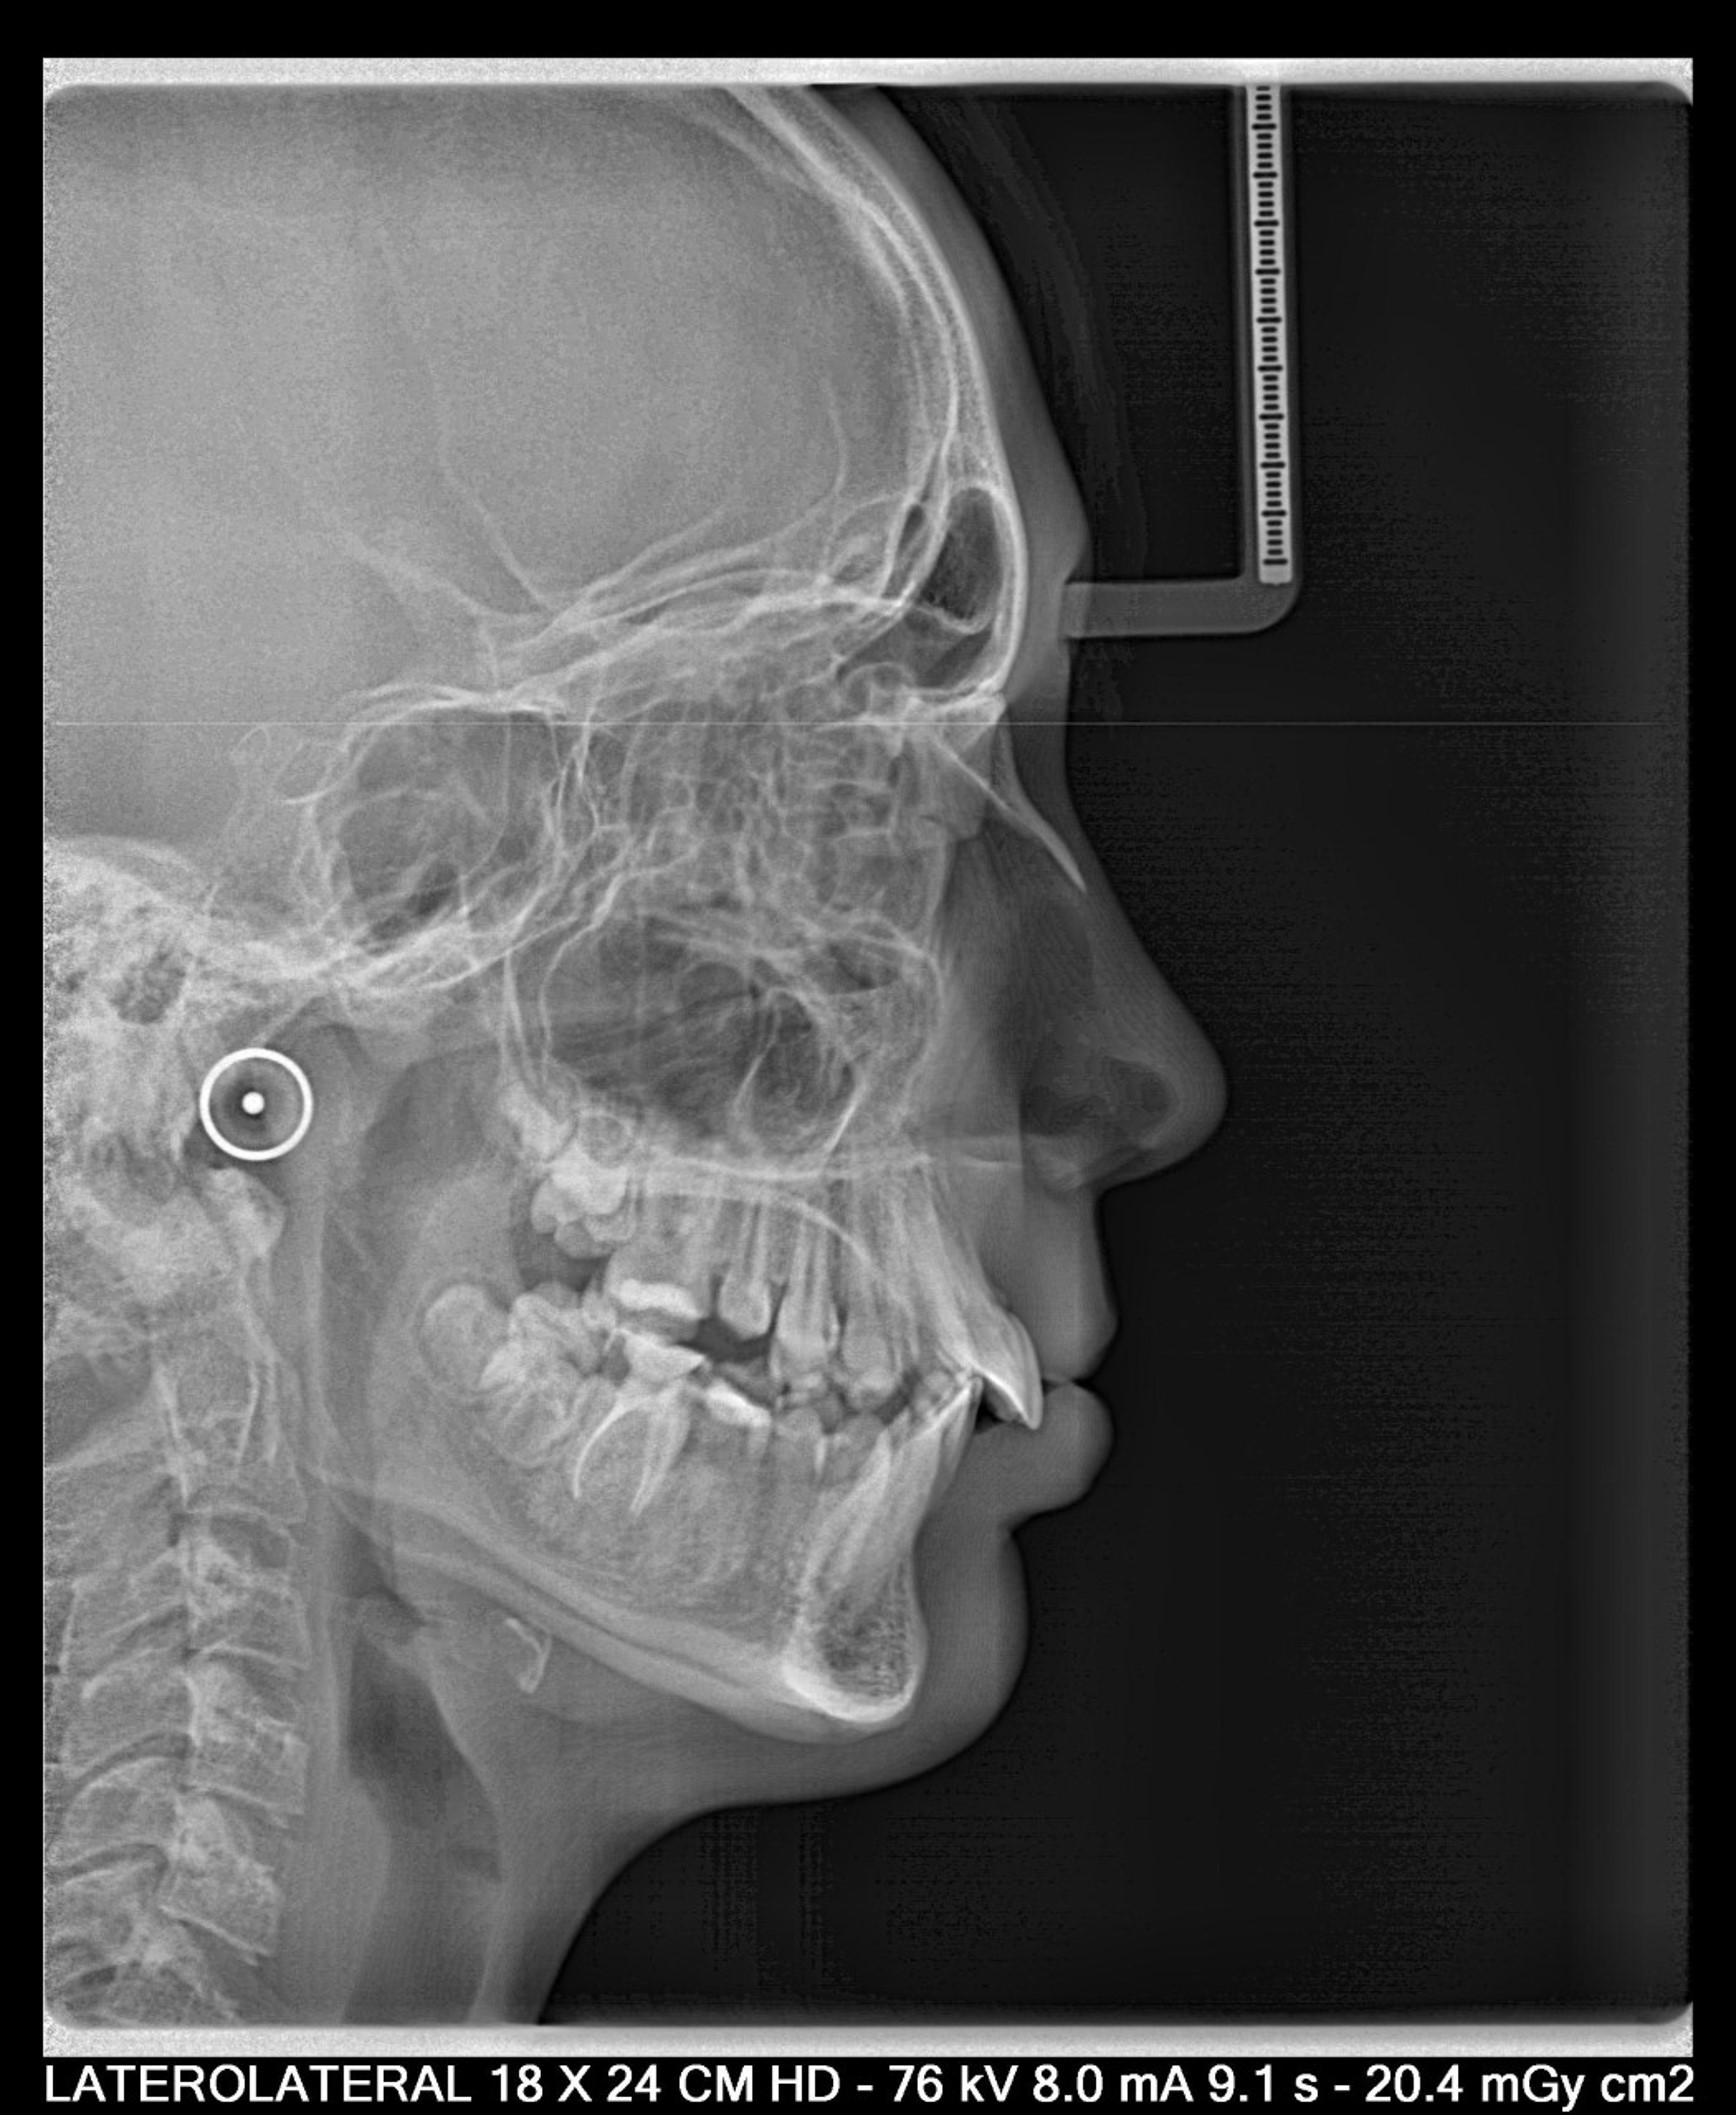

Nos encontramos con un caso en un timming adecuado para realizar un avance mandibular. También, nos favorece la inclinación el ángulo goniaco de 123 grados y la motivación del paciente. En contra nos perjudica la inclinación del incisivo inferior de 100 grados (lo podríamos controlar con microimplantes en la meseta inferior o alineadores, pero el paciente rechaza ambas opciones). Por otra parte,  en la radiografía frontal observamos un resto radicular en el 16, que decidimos extraer, y a petición del paciente, cerrar el espacio con mesialización del 17.

-¿Cuál sería el paciente ideal? El paciente con un ángulo goniaco favorable, braquifacial, inclinaciones con Incisvo superior protruido, e incisivo retruido, y donde el paciente es colaborador.

De hecho, según el ángulo Co-Go-Me, aquellos pacientes con un ángulo menor a 125,5 serán pacientes favorables para realizar una ortopedia de clase II , mientras  que aquellos pacientes con un ángulo mandibular mayor serán candidatos para realizar control vertical. De hecho, los pacientes con un ángulo mayor a 128 grados, tienen un desarrollo mandibular de 4,2mm, y aquellos con un ángulo menor a 123, tendrán una cantidad de crecimiento mandibular  de 7,3mm. Por lo tanto deducimos, que a mayor ángulo goniaco, habrá un menor crecimiento mandibular.